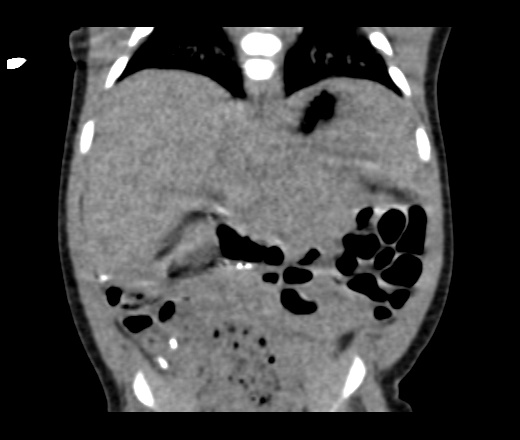

ΠΡΠΎΡΠΈΡΠ½ΡΠ΅ (ΡΠ΅ΠΊΡΠ½Π΄Π°ΡΠ½ΡΠ΅) ΠΈΠ·ΠΌΠ΅Π½Π΅Π½ΠΈΡ Π² ΠΏΠ΅ΡΠ΅Π½ΠΈ Π½Π° ΠΠ’. Π Π°ΠΊ ΠΊΠΈΡΠ΅ΡΠ½ΠΈΠΊΠ° Ρ ΠΌΠ΅ΡΠ°ΡΡΠ°Π·Π°ΠΌΠΈ. ΠΡΠΎΠ³Π½ΠΎΠ· Π½Π΅Π±Π»Π°Π³ΠΎΠΏΡΠΈΡΡΠ½ΡΠΉ, ΡΡΠΈΡΡΠ²Π°Ρ ΡΠ°Π·ΠΌΠ΅ΡΡ ΠΈ ΠΊΠΎΠ»ΠΈΡΠ΅ΡΡΠ²ΠΎ ΠΌΠ΅ΡΠ°ΡΡΠ°Π·ΠΎΠ².